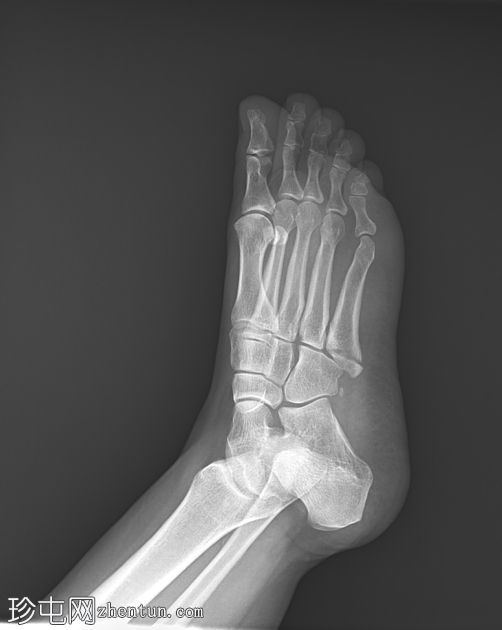

2.jpeg

斜位片

可见第五跖骨基底部粗隆(茎突)骨折。骨折线位于关节外,未延伸至第四至第五跖骨间关节。移位轻微。未见其他急性骨折。偶见腓骨副骨。